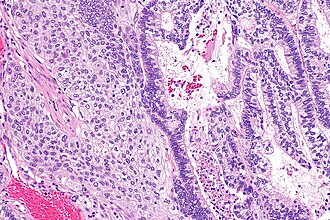

Adenosquamous carcinoma

Adenosquamous carcinoma is an uncommon epithelial neoplasm that has features of adenocarcinoma and squamous carcinoma. It is classified as a subtype of squamous carcinoma.[1]